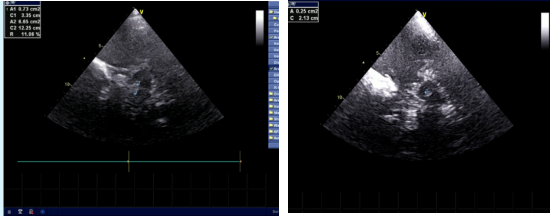

左图:正常黑质丨右图:黑质内高回声

帕金森病(PD)又叫震颤麻痹,是中老年比较常见的中枢神经系统病变之一,我国人口众多,人口老龄化问题比较严峻,帕金森病在老年人口中的发病率逐年增长,该病属于慢性神经系统疾病,临床症状一般表现为静止性震颤、行动迟缓、肌强直等。帕金森病主要的病理特点为中脑黑质多巴胺能神经元严重缺失和纹状体多巴胺神经递质减少。简而言之,中脑黑质的损害与帕金森病的发病直接相关。

黑质(substantia nigra, SN)是位于中脑的特殊结构,是调节运动的重要中枢。黑质是脑内合成多巴胺的主要核团,多巴胺也被称作“神奇的开心分子”;某些原因导致黑质细胞变性,造成多巴胺合成减少,这便是引起震颤麻痹的主要病因。